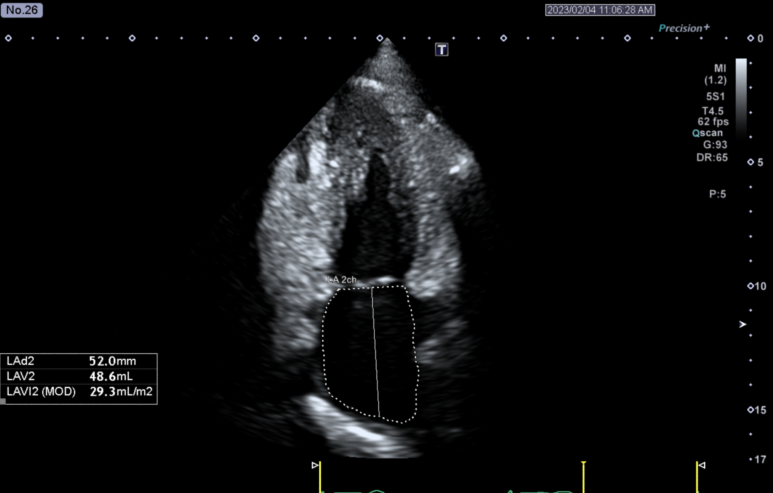

기침 > 심부전 진단된 환자분 심장(심비대)

심부전 (Heart Failure)

심장의 수축 기능이 떨어져 폐정맥 압력이 상승하면서 기침, 호흡곤란, 피로감, 하지 부종 등의 증상이 함께 나타납니다.특히 밤중에 숨이 차서 깨는 발작성 야간 호흡곤란, 누워서 숨이 찬 기좌호흡은 심부전을 강하게 시사하는 증상입니다.